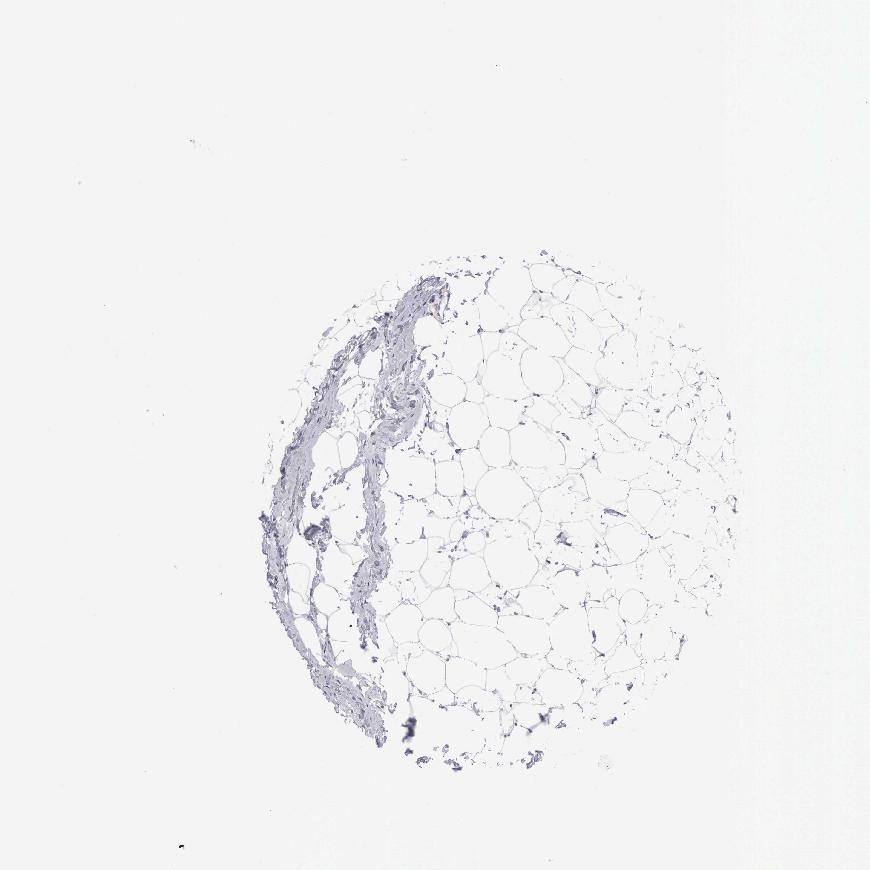

SOFT TISSUE 1 - Antibody stainingi

Antibody staining in the annotated cell types in the current human tissue is reported as not detected, low, medium, or high, based on conventional immunohistochemistry profiling in selected tissues. This score is based on the combination of the staining intensity and fraction of stained cells.

Each image is clickable and will lead to virtual microscopy that enables deeper exploration of all samples and also displays staining intensity scores, fraction scores and subcellular localization as well as patient and tissue information for each sample.

Antibody HPA000431

Fibroblasts Not detected